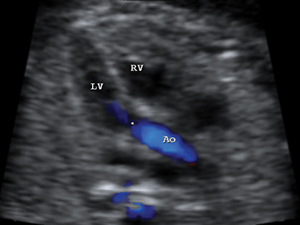

Heart